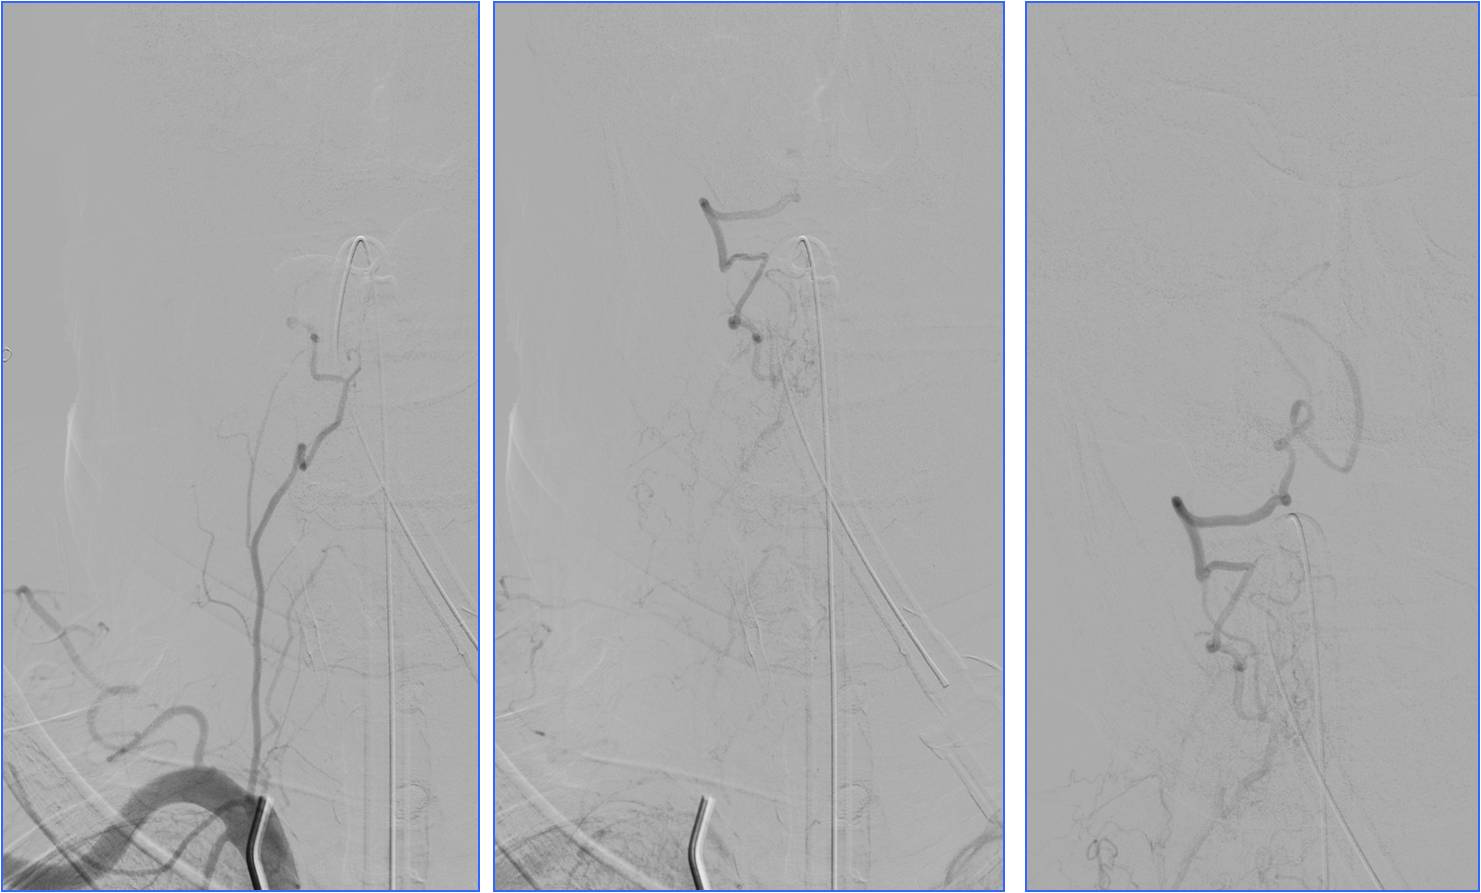

Case3 椎动脉开口支架置入

》男,68岁,有长期吸烟史。

》6:30突发晕厥1次伴头晕,7:00到急诊。7:30突然发作肢体抽搐伴意识不清。于8:10收入神经内科ICU。

》查体:血压140/60mmHg。中度昏迷,双侧瞳孔散大,光反应消失。四肢肌张力增高,去脑强直状态。双侧巴氏征阳性。NIHSS评分35分。

》昏迷前头CT检查(7:22)未见明显异常。

》昏迷后行头MRA检查。

▼7:22头CT

▼8:36头MRA

》急查血常规、凝血四项、肝肾电糖。

》签署静脉溶栓+动脉溶栓治疗知情同意书。

》8:54给予阿替普酶静脉溶栓,5mg静推,余45mg持续泵入。

》10:00股动脉穿刺。行气管插管全身麻醉。

▼于基底动脉远端及双侧大脑后动脉,分次给予阿替普酶共计5mg。

》12:10结束手术,带气管插管返回神经内科ICU。给予乌拉地尔持续泵入控制血压在110/70mmHg左右。

》第二天6:00出现中枢性高热,体温40℃。3天后转入普通病房。

》20天后出院,NIHSS评分5分。

▼溶栓后MRI